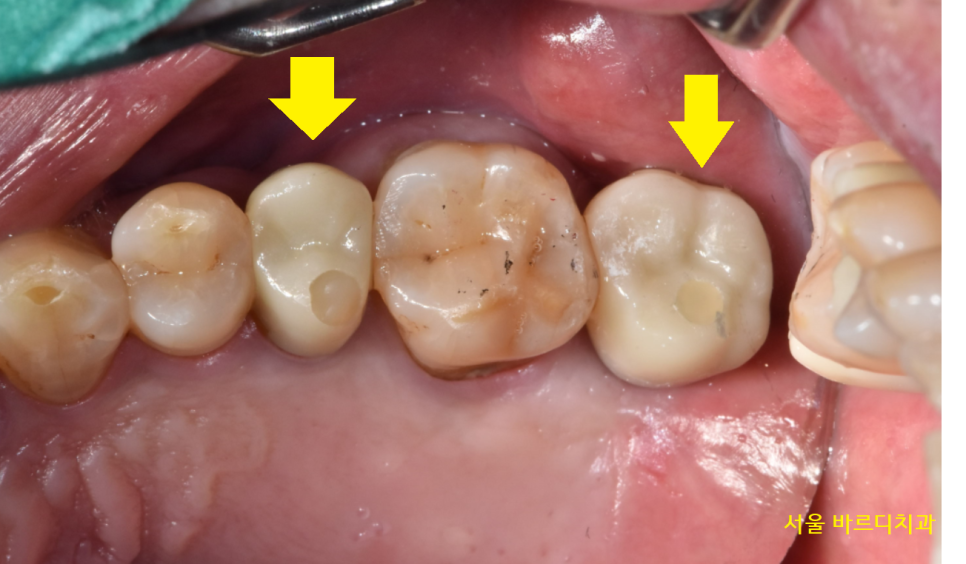

24.03.05

시간이 흘러 임플란트와 내 뼈가 잘 붙어서

보철을 만들어드렸습니다.